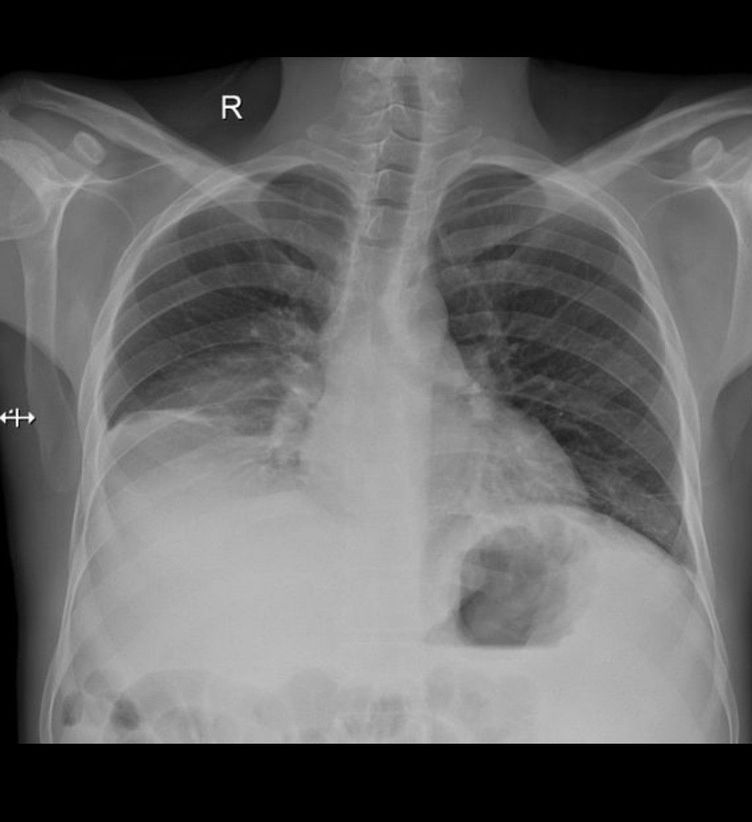

Diagnosis?

LVH + Right Plural effusion